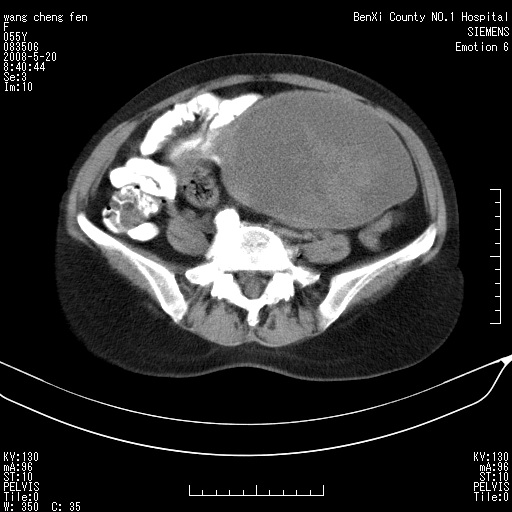

女、绝经后阴道流血3个月

左侧附件区可见一囊性占位,边缘清楚,内可见不规则形软组织影 ce:囊壁及内部可见强化 考虑 卵巢囊腺瘤

左侧附件区巨大囊实性病灶,边缘光整,病灶囊壁较厚,增强示囊壁及实性部分明显强化,强化呈度与宫体实质大致相同,宫腔积液征像,未见盆腔积液等其他异常,考虑左侧卵巢囊腺癌,不除外囊腺瘤及浆膜下肌瘤坏死

左侧附件区巨大囊实性病灶,边缘光整,病灶囊壁较厚,增强示囊壁及实性部分明显强化,强化呈度与宫体实质大致相同,宫腔积液征像,未见盆腔积液等其他异常。绝经后阴道流血3个月,结合病史左侧卵巢囊腺癌首先考虑,宫腔扩大不除外累及。期待结果。

支持浆膜下子宫肌瘤.之前由于网络原因未看全图片,现在重看,宫颈见一类圆形低密度影,增强轻度强化,低于肌层强化,宫腔扩大,考虑宫颈癌伴宫腔积液可能性大.

囊实性肿块分隔厚度较大,厚薄不均,增强实性成分明显强化,有不规则阴道流血,卵巢囊腺癌可能性大。

1,宫颈部占位,宫颈癌?2,左侧附件区囊实性占位,界较清,实质部分强化明显。考虑浆膜下或阔韧带肌瘤囊变可能大。囊腺类肿瘤不除外。